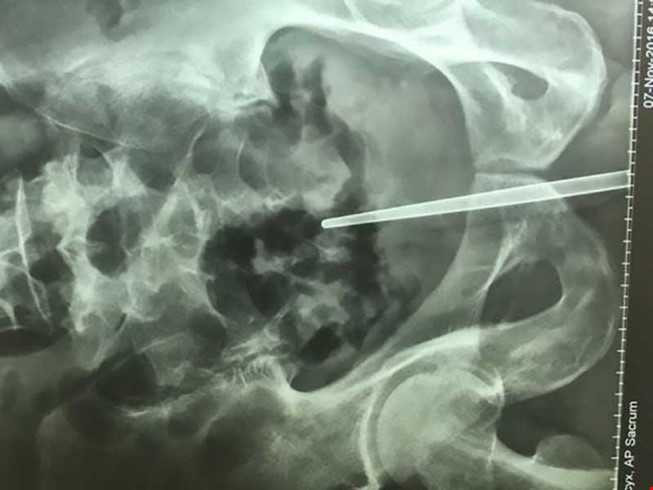

Hình ảnh chụp cắt lớp cho thấy cây đũa đã bị nhét sâu trong dương vật

Hình ảnh chụp cắt lớp cho thấy cây đũa đã bị nhét tới tận thành trực tràng ông này. Theo các bác sĩ, nếu cây đũa bị đẩy sâu thêm chút nữa thì rất có thể ông Chen đã tử vong.

Các bác sĩ phải phẫu thuật mới lôi được cây đũa dài 18 cm làm bằng kim loại không thấm nước ra khỏi dương vật ông Chen chơi dại này.